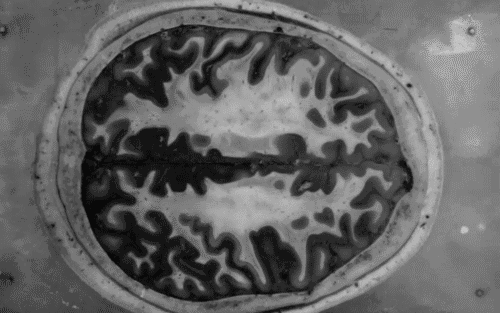

Uskoro bismo si mogli 'brisati' mozak?

Iako je moguće, ne znači da bi se trebalo raditi. Upravo tako se može sažeti ovo posljednje znanstveno postignuće.

Vjerojatno ste bar jednom poželjeli potpuno zaboraviti na neki nemili događaj iz dvog života. Takvo što se do sad činilo tek poput zapleta nekog prosječnog SF filma, no uskoro bi moglo postati stvarnost. Znanstvenici sa Sveučilišta u Torontu uspjeli su kod laboratorijskih miševa izolirati određene 'neurone straha' i izbrisati iz njihova sjećanja traumatična iskustva bez da taknu o ostala sjećanja.

Smatraju kako bi takva metoda mogla biti primijenjiva i na ljude, no takvo što bi sa sobom potegnulo goleme etičke dileme. Iako bi se 'brisanje sjećanja' moglo koristiti za liječenje oboljelih od PTSP-a, kao i ovisnika o drogama, brisanje loših sjećanja onemogućilo bi nam da učimo iz vlastitih grešaka, jer ako iz sjećanaj izbrišemo neku grešku koju smo počinili - što nas sprječava da je ne ponovimo?

I sami stručnjaci koji su radili na ovoj studiji kažu da iako je nešto moguće napraviti, ne znači da bi se i trebalo raditi.

'Zaključili smo kako je brisanje sjećanja moguće, ali društvo mora razviti napredne etičke odrednice koje bi se ticale ove prakse', kaže prof.dr. Sheena Josselyn, voditeljica ove studije.